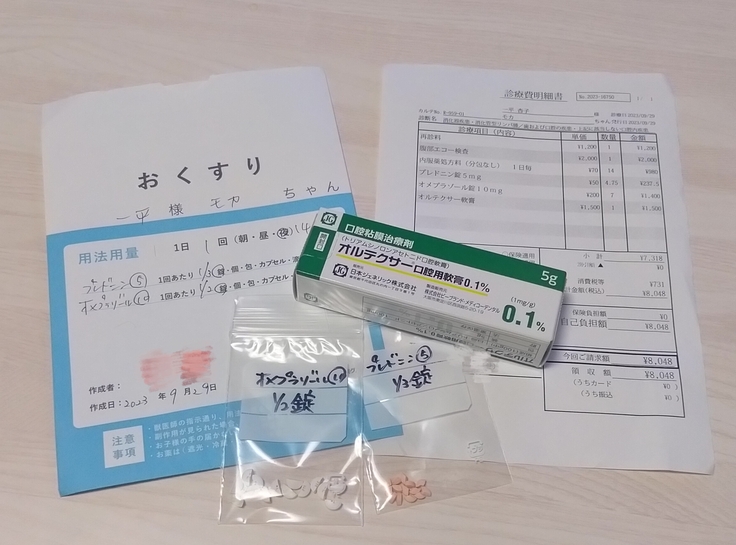

実は先週から鼻下と上唇裏に謎の腫れが出来、通院や投薬(ステロイド増量)をしていたのですが、そちらも短期間で治ったので問題なしとのことで、ステロイド卒業に向けて再びちょっとずつ減薬していくことに!💊

↑念の為軟膏が処方されましたが、また皮膚にアレルギー的症状が出た時用のお守りです💊

今回一時的ではありますがステロイドを増量したので血液検査はなし!(正確な現在の数値が測れない為)2週間後にまた通院で経過観察することになりました🏥